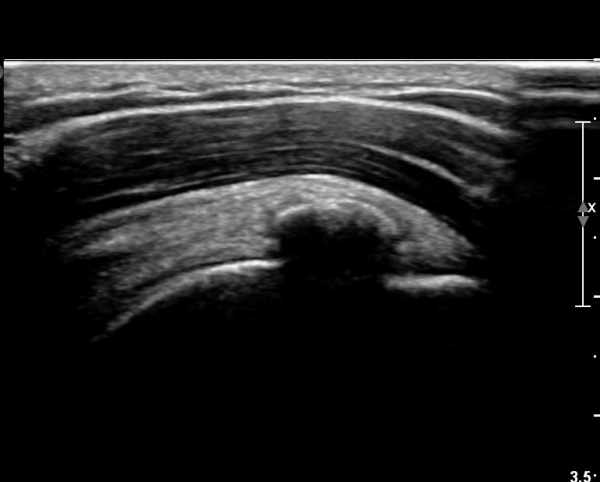

ÃÊÀ½ÆÄ ¼Ò°ß :  ±Ø»ó°Ç Á¾´Ü¸é°Ë»ç¿¡¼­ ÈĹæÀ½¿µÀ» º¸ÀÌ´Â °í¿¡ÄÚ ¼®È¸È­ µ¢¾î¸®°¡ °üÂûµÈ´Ù(»çÁø 1).